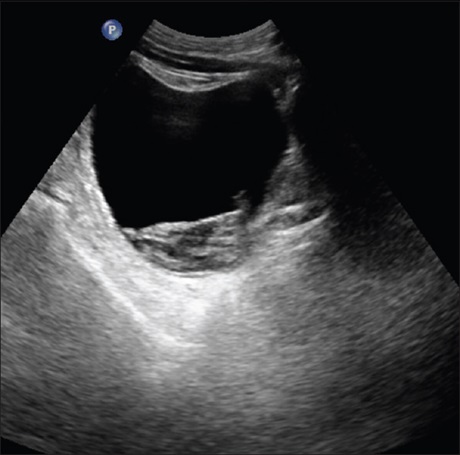

Further observations on the “spaghetti sign” in upper urinary tract hemorrhage

Prof. Funsho Komolafe, Sabir Hussain, Syed Waqar Hussain (Author)

136-140